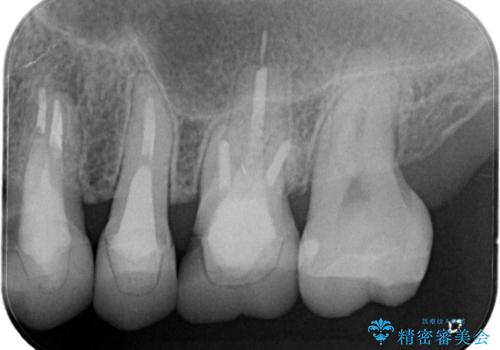

【オールセラミッククラウン】プラスチックの被せ物が壊れた。

- 以前他院で治療した被せ物が壊れたことを主訴に来院されました。

強度に優れたオールセラミッククラウンにて治療を行なっております。

3歯同時に治療を行うこと来院回数は4回で終了しています。